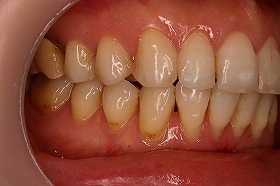

この患者様は、非抜歯で矯正治療を進めることができ、

治療後は上下の噛み合わせもよくなりました。